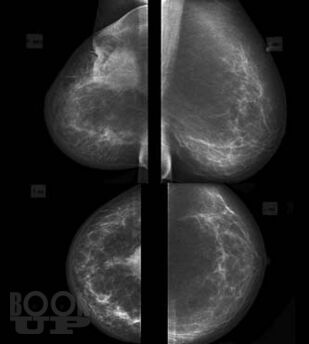

В основу книги положены материалы собственных исследований авторов и практический опыт использования комплекса новейших методик ультразвукового исследования в диагностике рака молочной железы, изучении состояния регионарных зон лимфоотока. Цель книги – помочь практикующим специалистам ультразвуковой, лучевой диагностики, маммологам, гинекологам, врачам общей практики систематизировать знания по эффективному использованию в своей практике новейших технологий ультразвукового исследования, обучить основам комплексной первичной и дифференциальной диагностики патологии молочных желез. Издание хорошо иллюстрировано, содержит большое количество рисунков, эхограмм.